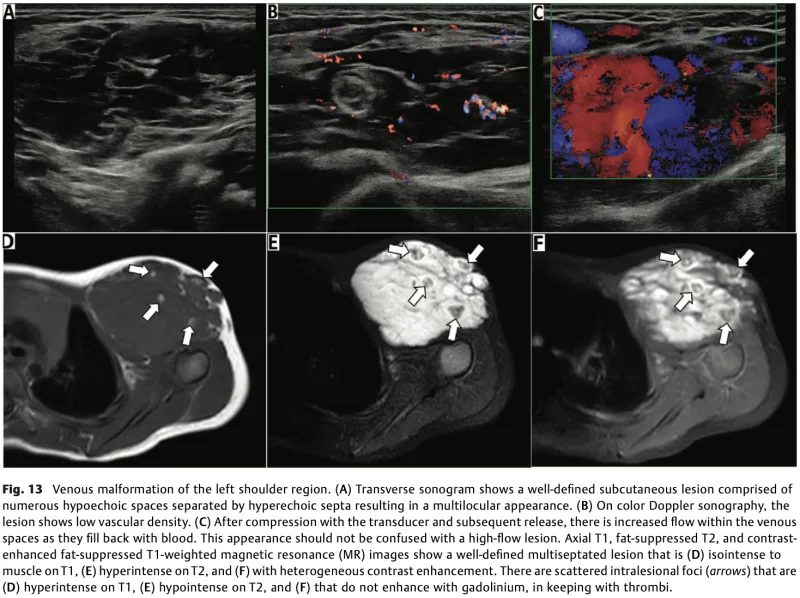

MRIでは, 腫瘤部野中に血液の塊(血栓)(図中の→)を認めます.

もう一人の中高年の背部腫瘍の患者さんは, 一時痛みがあったものの緩和傾向とのこと.

触診上は柔らかく, 血管腫(正確には, 血管奇形)か脂肪腫を疑いました.

お二人とも, 造影MRIを撮像して, 診断することにしました.

予想通りに, 内軟骨腫と血管(静脈)奇形と診断.

血管奇形の患者さんは, 当科外来で定期的に経過を観察することに.